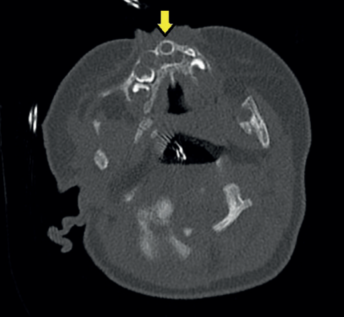

A los 50 días de vida consulta en urgencias por dificultad respiratoria y rechazo de las tomas secundarios a infección respiratoria superior agravada por la anatomía de la paciente. A la exploración física se evidencia paladar ojival en V, hipotelorismo, raíz nasal plana con anteversión de narinas (ya objetivados en controles de seguimientos previos, más evidentes con el crecimiento de la paciente). Se decide ampliar estudio con TAC de cabeza y senos paranasales donde se objetiva estenosis de orificios piriformes (Figura 1) (derecho de 4 mm, izquierdo de 1,2 mm) por medialización del proceso nasal del hueso maxilar que asocia desviación del tabique nasal al lado izquierdo junto a paladar duro hipoplásico con morfología triangular y megaincisivo central único en maxilar superior (Figura 2). Se realiza resonancia magnética (RM) cerebral donde no se visualizan otras alteraciones en cerebro, cerebelo o tronco con hipófisis presente en silla turca de aspecto normal. Se realiza nasofibrolaringoscopía objetivando estrechez de narinas y fosas nasales que dificulta el paso del fibroscopio hasta laringe. Radiografía de tórax y serie ósea, ecografía abdominal, ecocardiografía sin alteraciones. Estudio analítico (incluido perfil tiroideo) normal. Es dada de alta con alimentación por sonda nasogástrica bajo seguimiento estrecho en consultas de dismorfología, donde se completa estudio genético con cariotipo 46 XX y CGH Array en el que no se detectan variaciones de cambio de número de copia de naturaleza no polimórfica.

Figura 1: TAC craneal. Estenosis de la apertura piriforme < 11 mm